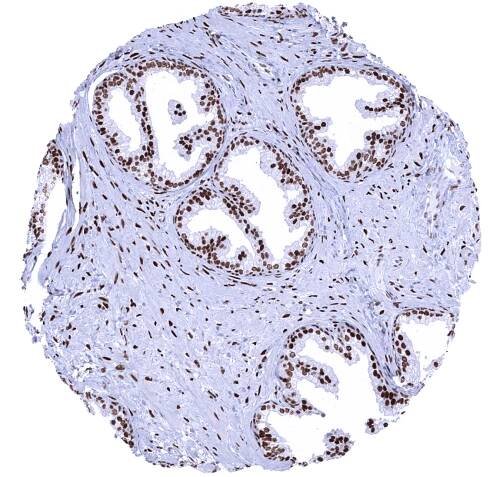

Prostate - A strong nuclear Androgen Receptor immunostaining is seen in stromal and epithelial cells of the prostate.